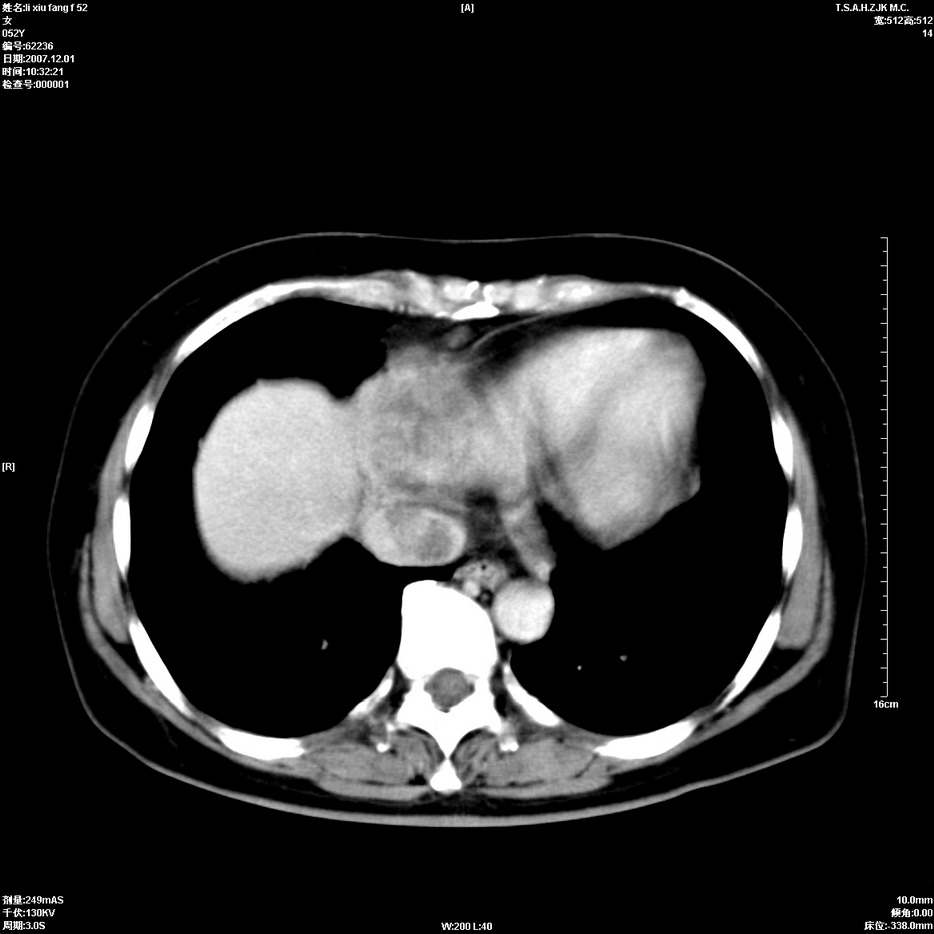

标题: CT12858:女,52岁,胎甲球蛋白861肝左叶占位,肝癌。下腔静 [打印本页]

标题: CT12858:女,52岁,胎甲球蛋白861肝左叶占位,肝癌。下腔静

肝左叶巨大低密度灶肿块,增强符合快进快出表现,有动静脉交通支;静脉期,下腔静脉内有充盈缺损,afp明显升高,支持肝癌并下腔静脉癌栓形成。

以下是引用拾荒者在2008-4-15 22:57:00的发言:[br]肝左叶巨大低密度灶肿块,增强符合快进快出表现,有动静脉交通支;静脉期,下腔静脉内有充盈缺损,afp明显升高,支持肝癌并下腔静脉癌栓形成。